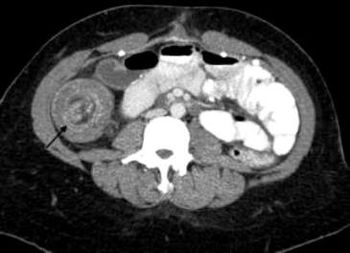

Cutaneous hyperpigmentation and papules coupled with active GI bleeding and a submucosal mass. What’s the diagnosis-and the chief clinical concern?